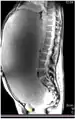

MRI giant serous cystadenoma of ovary